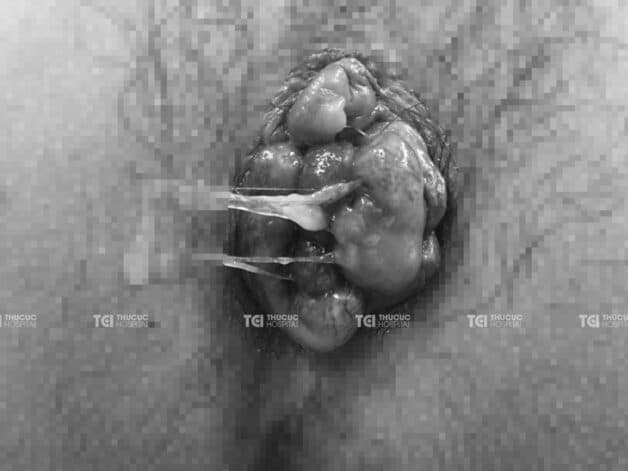

Hình ảnh búi trĩ ở giai đoạn nặng trên thực tế